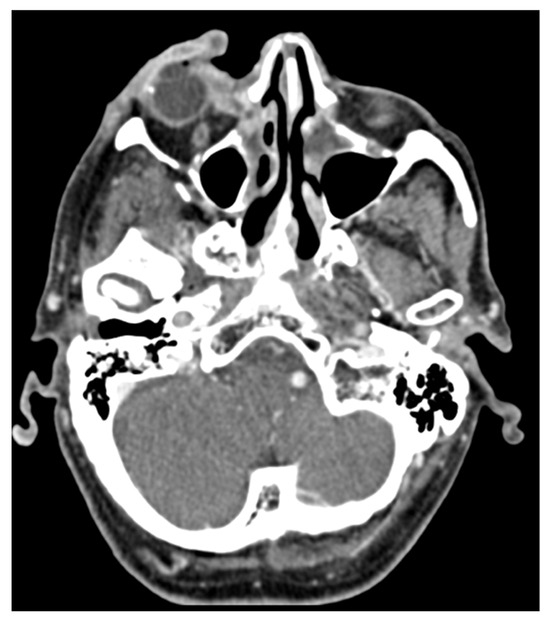

7. The Role of Imaging in Cutaneous Squamous Cell Carcinoma

8. Follow-Up Imaging

- Humphreys, T.R.; Shah, K.; Wysong, A.; Lexa, F.; MacFarlane, D. The role of imaging in the management of patients with nonmelanoma skin cancer: When is imaging necessary? J. Am. Acad. Dermatol. 2017, 76, 591–607, Erratum in J. Am. Acad. Dermatol. 2017, 76, 1226. [Google Scholar] [CrossRef] [PubMed]

- MacFarlane, D.; Shah, K.; Wysong, A.; Wortsman, X.; Humphreys, T.R. The role of imaging in the management of patients with nonmelanoma skin cancer: Diagnostic modalities and applications. J. Am. Acad. Dermatol. 2017, 76, 579–588. [Google Scholar] [CrossRef] [PubMed]

- Williams, L.S.; Mancuso, A.A.; Mendenhall, W.M. Perineural spread of cutaneous squamous and basal cell carcinoma: CT and MR detection and its impact on patient management and prognosis. Int. J. Radiat. Oncol. Biol. Phys. 2001, 49, 1061–1069. [Google Scholar] [CrossRef] [PubMed]